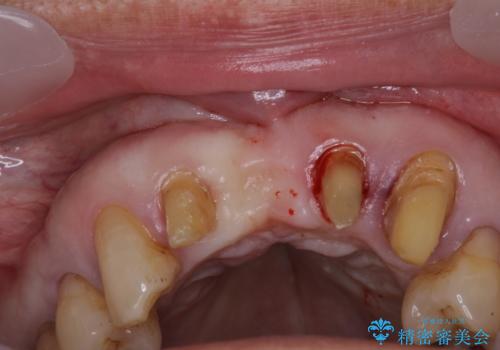

- 上の前歯が痛むとのことで来院された患者様です。

検査を行ったところ、前歯1本は周辺の骨が失われており、抜歯が必要でした。

上顎の奥歯は全体的に歯周ポケットが散見され出血が認められたため、歯周外科処置を行うこととしました。

上の歯は見た目を良くしたいというご希望があったため、歯周外科処置を行った歯についてはセラミッククラウンで補綴することとしました。